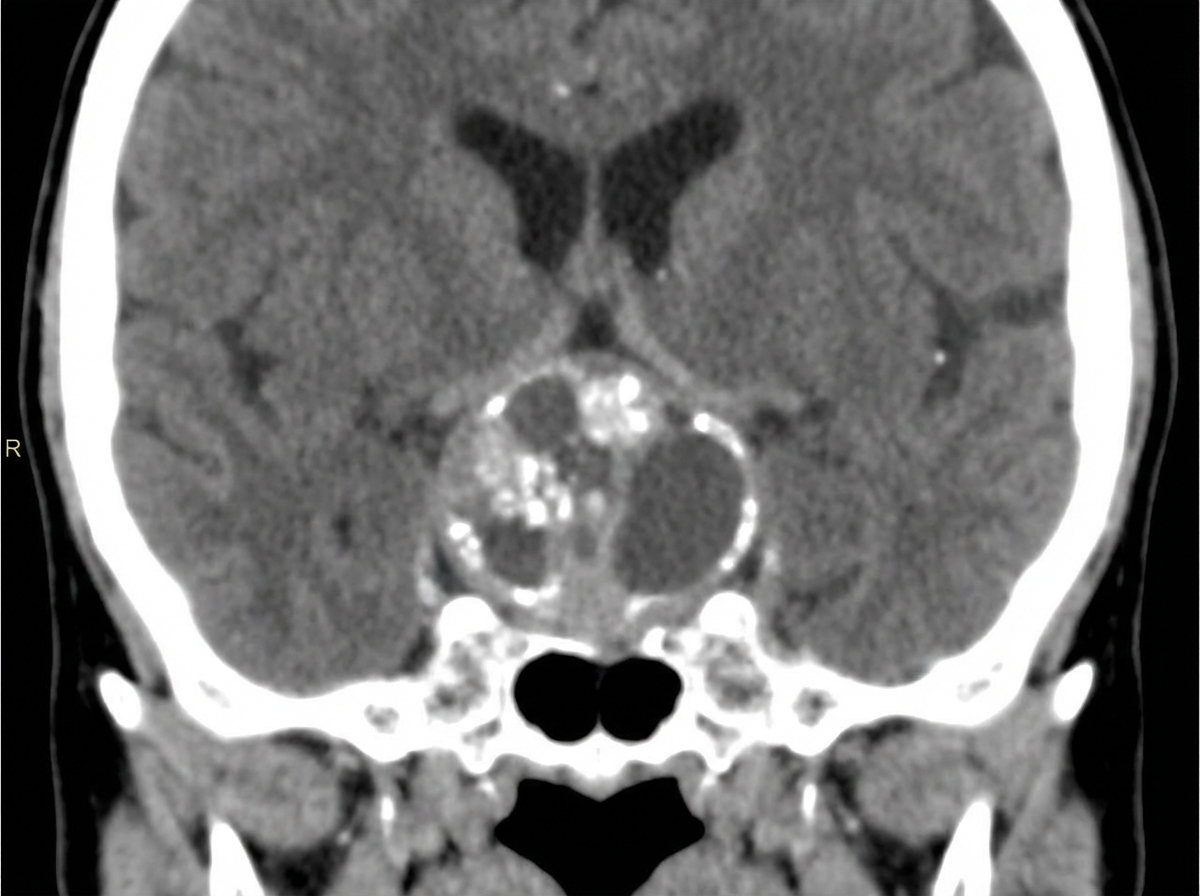

What is the diagnosis for a 10-year-old child presented with vision problems, given the CT scan below?

Explanation: ***Craniopharyngioma*** - Most common **suprasellar tumor** in children, typically presenting with **visual field defects** due to **optic chiasm compression**. - Classic CT features include **calcifications** (90% in children) and **cystic-solid mixed appearance** in the suprasellar region. *Pituitary macroadenoma* - Extremely rare in **pediatric patients** and typically presents with **endocrine dysfunction** rather than isolated vision problems. - CT shows **homogeneous enhancement** without the characteristic **calcifications** seen in craniopharyngiomas. *Germinoma* - More commonly affects the **pineal region** rather than suprasellar area, causing **Parinaud syndrome** and **hydrocephalus**. - CT typically shows **homogeneous hyperdense mass** without calcifications and responds dramatically to **radiation therapy**. *Lipoma* - Appears as **hypodense lesion** with **fat attenuation** (-50 to -100 HU) on CT, distinctly different from craniopharyngioma. - Usually **asymptomatic** and rarely causes **mass effect** or visual disturbances in children.